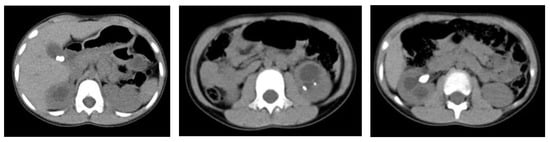

2. Case Presentation